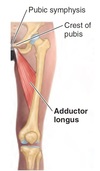

What are the origin and insertion sites for muscle A?

Origin - External body of pubis (inferior to pubic crest and lateral to pubic symphysis)

Insertion - Linea aspera on middle 1/3rd of femoral shaft

A - Adductor longus